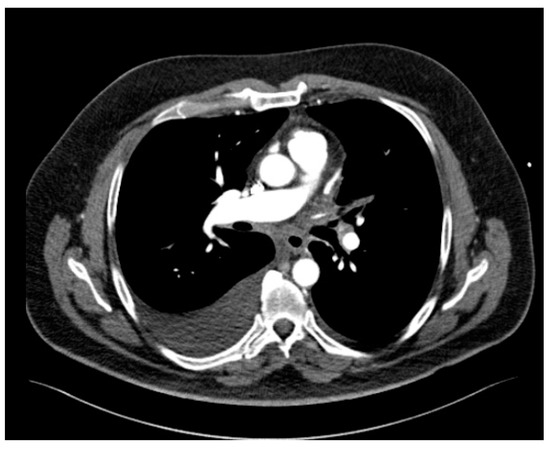

Upon admission, the patient was in sinus rhythm with no atrial fibrillation episodes at Holter monitorization. Transthoracic echocardiography showed moderate dilation of right heart cavities, severe pulmonary hypertension (70 mmHg), and a turbulent flow in superior pulmonary veins (Figure 1). Pneumological evaluation revealed a mild restrictive dysfunction with a blood oxygen level of 95%. As the patient was under treatment with Eliquis® (apixaban), pulmonary embolism was not suspected. Given his history of radiofrequency ablation for atrial fibrillation, the cardiologist scheduled the patient for a cardiac CT angiography to exclude a post-procedural stenosis of the pulmonary veins.

The CT study revealed stenosis of all four pulmonary veins (severe stenosis of the right superior, right inferior and left inferior PVs, near-occlusion of the left superior PV and of the vein draining the apical segment of the right lower lobe) (Figure 2).

Figure 2.

Cardiac CT angiography revealing stenosis of all four pulmonary veins: (a) maximum intensity projection (MIP) reconstruction; (b) volume rendering technique (VRT) reconstruction.